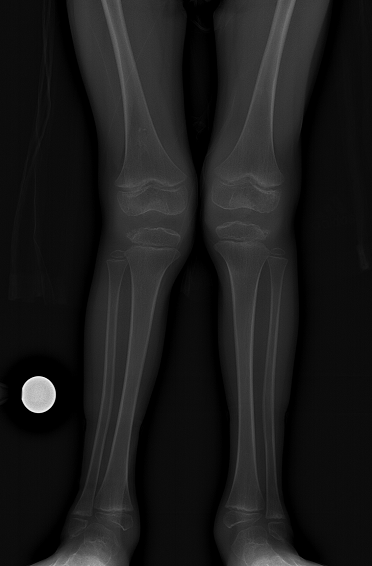

Our 6 year old son Cooper has a rare, progressive disease called MPS IVA. It affects every organ of his body (except his brain), and has SEVERE skeletal implications. We are blessed to have a weekly infusion to slow/stop the progression of the damage to his organs, but the only way to address the skeletal issues is with surgery. It’s time for the first Orthopedic intervention.

Cooper will have surgeries on both hips, knees and ankles in June. This will relieve the constant pain in my first grader’s hips and knees and keep him mobile for a while longer. The surgeries will be done by Dr. Mackenzie in Wilmington, Delaware. He’s the orthopedic expert on Cooper’s condition, so that’s where we’re going.